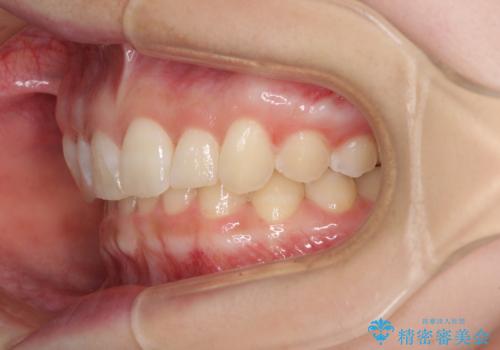

前歯のデコボコを治したい インビザライン矯正治療

- 前歯のデコボコ気になるとのことで来院された患者様です。

下顎骨が上顎骨に対して右側にシフトしており、さらに下顎が後方に位置しているため、非常に強い咬合力で食いしばっている状態でした。

上下顎ともに歯列全体の後方移動とIPR(歯と歯の間を削る)によってデコボコが解消するように設計し、インビザラインにより治療を行うこととしました。

強い咬合力による臼歯部の噛みにくさと、それに伴う歯の移動の鈍さに悩まされ、非常に長い期間を要することとなりました。

上下正中位置は、治療開始時よりは改善したものの、ここが限界であろうというところでのゴールとなりました。

下顎前歯の大半が隠れている状態ですが、左右への歯ぎしりはスムーズに行うことができ、就寝時には後戻り防止も兼ねて、食いしばり対策としてマウスピースの使用を継続するようお願いしております。